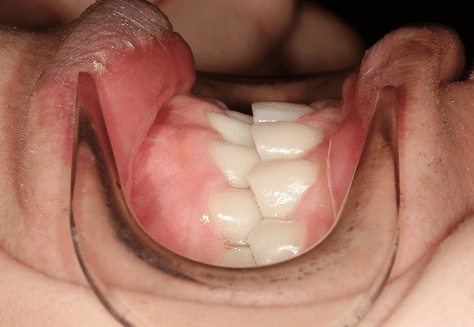

M.U

治療前

治療後

主訴

下の歯が特にガタガタなのが気になる。上の前歯が1本反対になっている。

診断

下顎前突・叢生・反対咬合

年齢/性別

20代/男性

抜歯部位

非抜歯

使用装置

上下インビザライン(PBM使用)

保定装置

ビベラリテーナー

診察料金

5,500円×16回

治療期間

1年7カ月